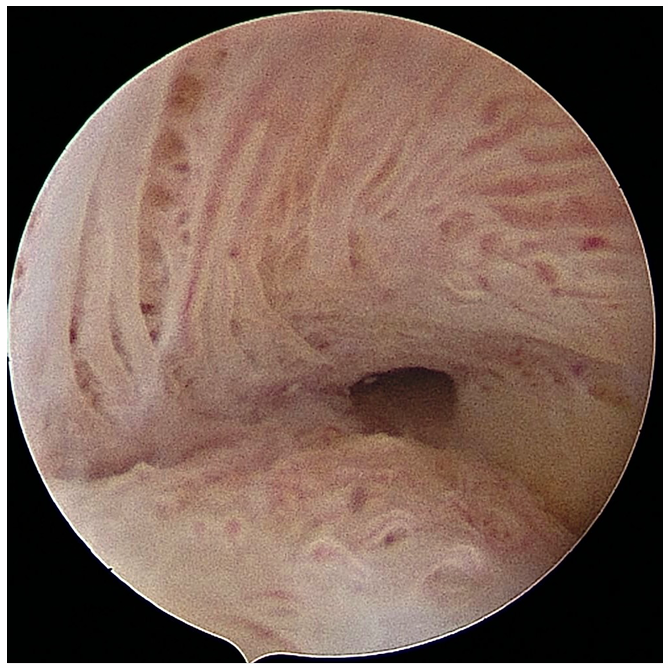

A hysteroscopy is a procedure that allows your doctor to look inside your uterus (womb) to diagnose and treat causes of abnormal bleeding or fertility issues. We use a hysteroscope-a thin, lighted telescope-like instrument. It is inserted through the vagina and cervix into the uterus. Because it enters through natural pathways, there are no cuts or incisions on your skin.

● Infertility Evaluation: To check for blockages, scar tissue, or uterine shapes (like a septum) that might prevent pregnancy.

● Recurrent Miscarriage: To identify if uterine abnormalities are causing pregnancy loss.

4. We release a fluid (usually saline) to expand the uterus, giving us a clear view of the lining and the openings of the fallopian tubes.